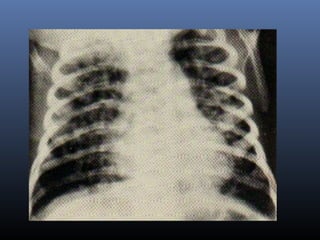

TAQUIPNÉIA TRANSITÓRIA DO RN

 ACHADOS RADIOLÓGICOS

Hiperinsuflação

Discreta cardiomegalia

Estrias peri-hilares

Edema dos septos inter-lobares

Infiltrados alveolares, traduzindo edema alveolar

Mínimo derrame pleural no seio costofrênico.

♦ Essas imagens são características de “edema”do

pulmão.

TAQUIPNÉIA TRANSITÓRIA DORN  ACHADOS RADIOLÓGICOS Hiperinsuflação Discreta cardiomegalia Estrias peri-hilares Edema dos septos inter-lobares Infiltrados alveolares, traduzindo edema alveolar Mínimo derrame pleural no seio costofrênico. ♦ Essas imagens são características de “edema”do pulmão.